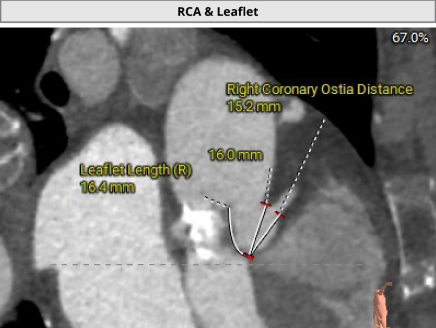

冠脉阻挡风险及钙化评估

2. 冠脉开口高度尚可,左右冠瓣叶冗长,切线位左右冠瓣叶长度>>冠脉开口到瓣叶根部附着缘距离;冠脉未见明显钙化斑块;

• 左右冠瓣叶冗长,切线位左右冠瓣叶长度>>冠脉开口到瓣叶根部附着缘距离,结合瓦氏窦、STJ、钙化分布特点综合预估冠脉堵塞风险偏高,术中球扩时密切关注冠脉血流灌注,备冠脉保护方案;